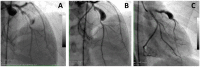

Coronary artery aneurysms (CAAs) are uncommon and describe a localized dilatation of a coronary artery segment more than 1.5-fold compared with adjacent normal segments. The incidence of CAAs varies from 0.3 to 5.3%. Ever since the dawn of the interventional era, CAAs have been increasingly diagnosed on coronary angiography. Causative factors include atherosclerosis, Takayasu arteritis, congenital disorders, Kawasaki disease (KD), and percutaneous coronary intervention. The natural history of CAAs remains unclear; however, several recent studies have postulated the underlying molecular mechanisms of CAAs, and genome-wide association studies have revealed several genetic predispositions to CAA. Controversies persist regarding the management of CAAs, and emerging findings support the importance of an early diagnosis in patients predisposed to CAAs, such as in children with KD. This review aims to summarize the present knowledge of CAAs and collate the recent advances regarding the epidemiology, etiology, pathophysiology, diagnosis, and treatment of this disease.